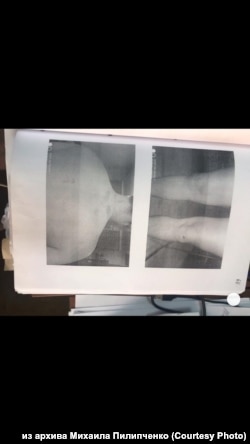

Побои Михаила Пилипченко, зафиксированные судмедэкспертом

– Конечно, я, получается, главный свидетель. Не исключаю, что именно из-за этого на меня уголовное дело завели – репутацию как свидетелю испортить. 17 июня меня вызвали как свидетеля. А буквально через несколько дней уже как подозреваемого опрашивали. Плюс следователь мне "забыла" выдать направление на судмедэкспертизу, а без нее ты побои не снимешь так, чтобы суд это принял. В итоге я только через месяц их снял, когда гематомы уже спали, синяки уже проходили.